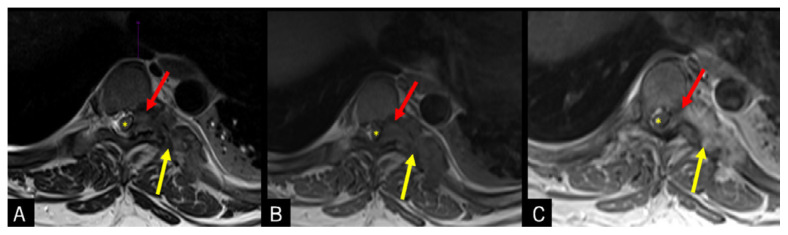

Tophaceous Gout in the Axial Skeleton: An Unusual Case with Key Imaging Characteristics.